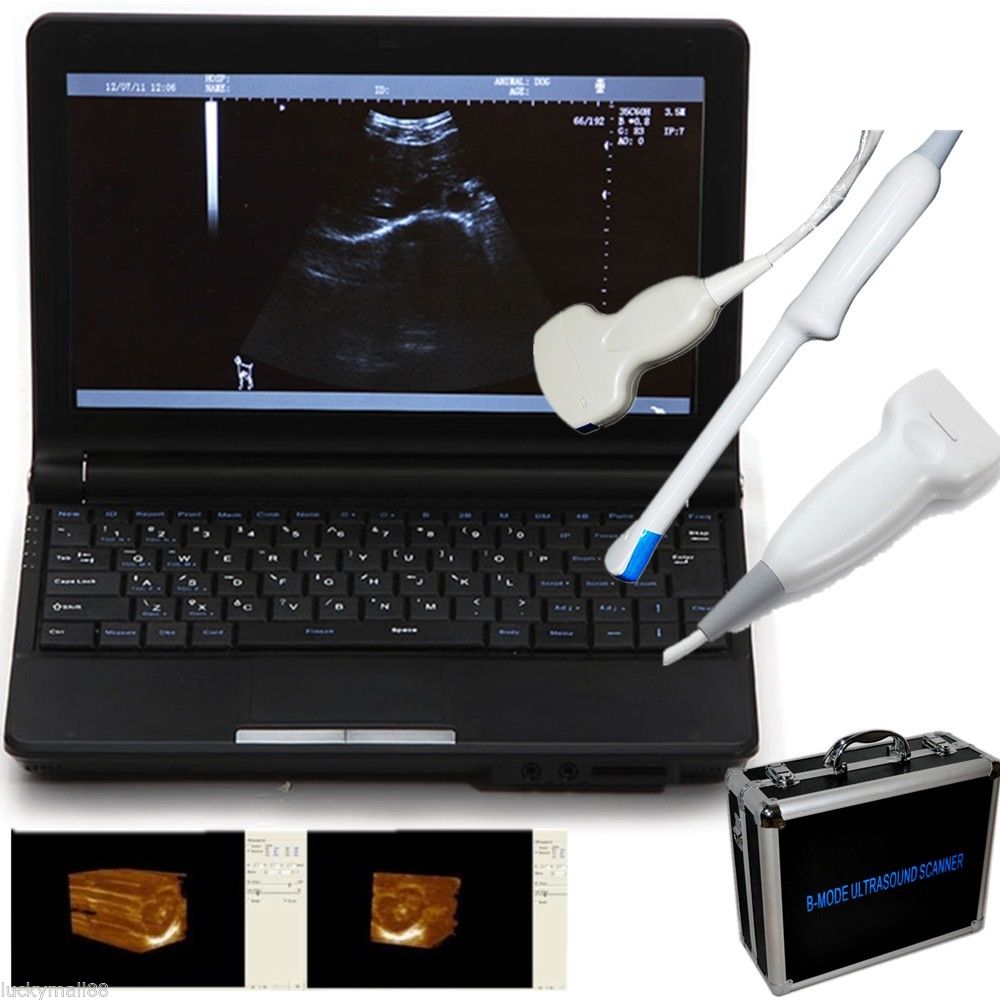

Explore the Benefits of Our Portable Ultrasound Scanner

Advanced Features for Accurate Diagnostics

Our portable ultrasound scanner is equipped with cutting-edge technology that improves diagnostic accuracy. With its convex linear transvaginal probe, it allows for detailed imaging of internal structures. The tool is designed to be user-friendly, meaning healthcare professionals can easily operate it without extensive training. Therefore, its advanced features can help in making quick and informed decisions in clinical settings, which is essential for patient care.

Compact and Convenient Design

The scanner’s compact design makes it highly portable, allowing healthcare providers to conduct examinations in various settings. Whether it is a clinic or a hospital, this ultrasound machine can be easily transported. Healthcare professionals appreciate its lightweight structure, so they can perform immediate diagnostics without being tied to a fixed location. Because of its convenience, this device enhances the delivery of healthcare services.

Versatile Application in Obstetrics and Gynecology

This portable ultrasound scanner is particularly beneficial in obstetrics and gynecology, as it provides clear and detailed images necessary for monitoring pregnancies and diagnosing conditions. Its transvaginal probe allows for a closer view of reproductive organs, which helps in identifying issues early on. Consequently, this versatility ensures that healthcare professionals can use it in various procedures, making it an essential tool in women’s health.